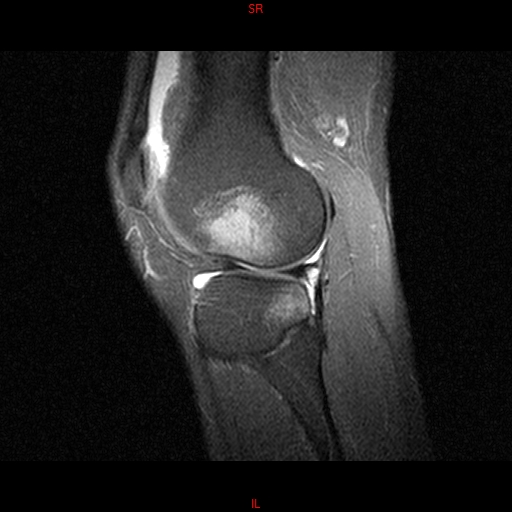

• RESONANCIA PATOLÓGICA MENISCOPATIA INTERNA DP SAGITAL

• RESONANCIA NORMAL RODILLA SAG DENSIDAD PROTONICA

• RESONANCIA NORMAL RODILLA SAG T1